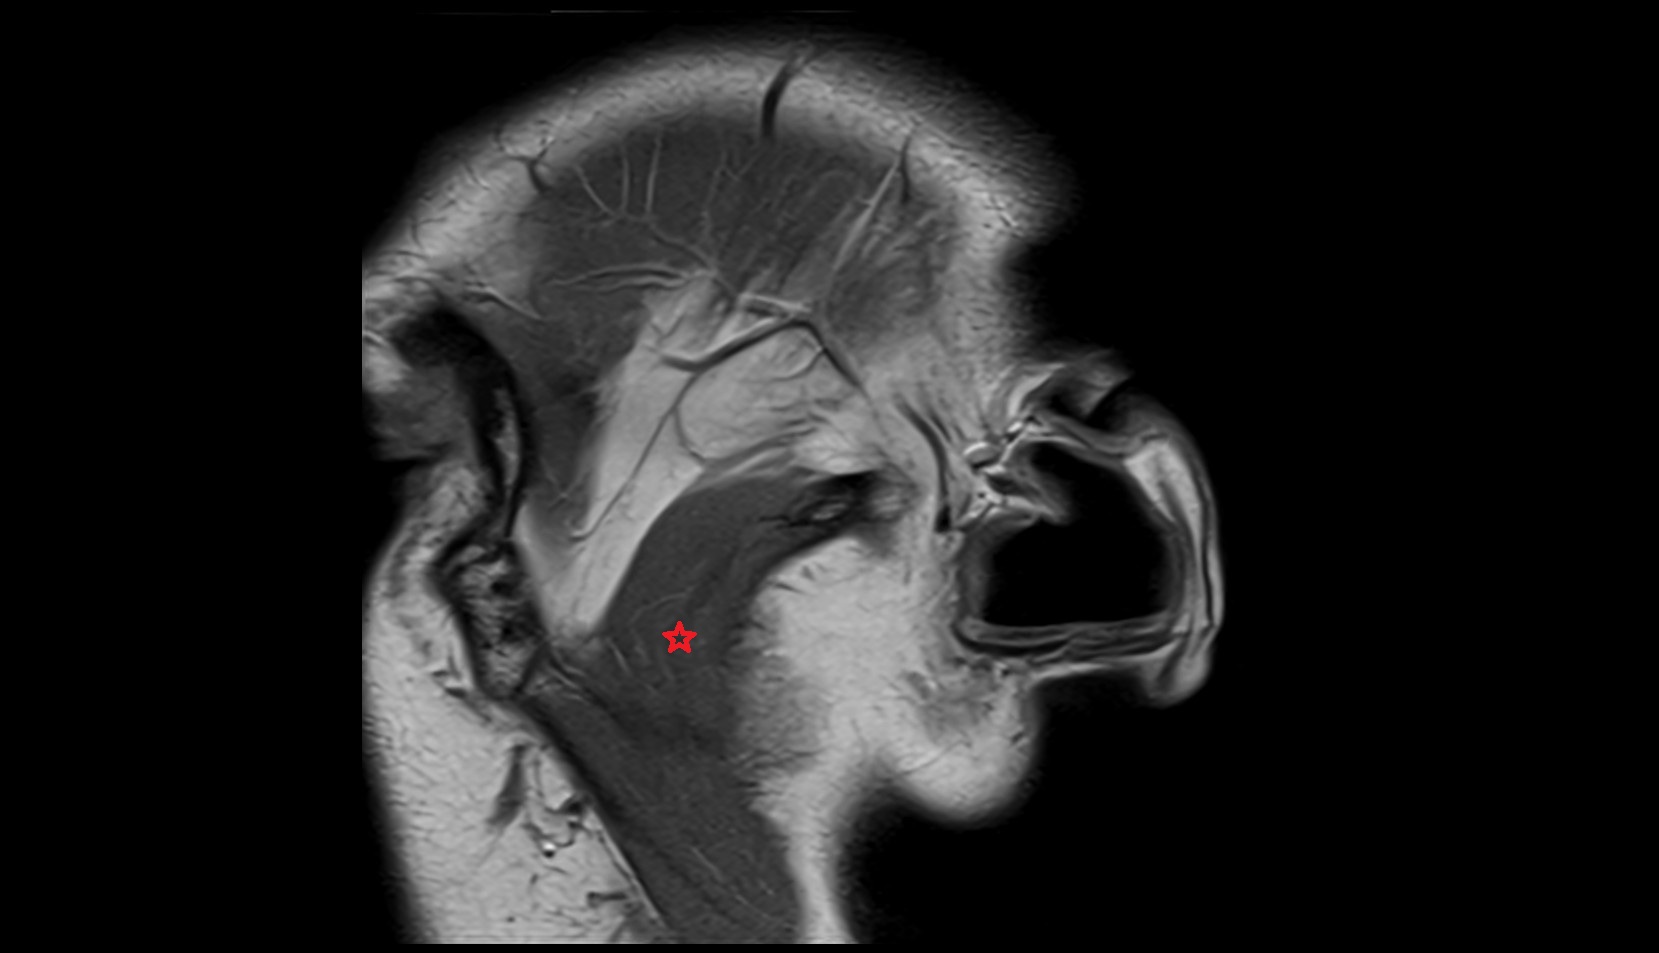

- Fetal brain

- Fetal caudate nucleus

- Fetal thalamus

- Fetal pons

- Fetal cerebellum

- Fetal occipital lobe

- Fetal temporal lobe

- Fetal parietal lobe

- Fetal frontal lobe

- Fetal third ventricle

- Fetal fourth ventricle

- Fetal lateral ventricle